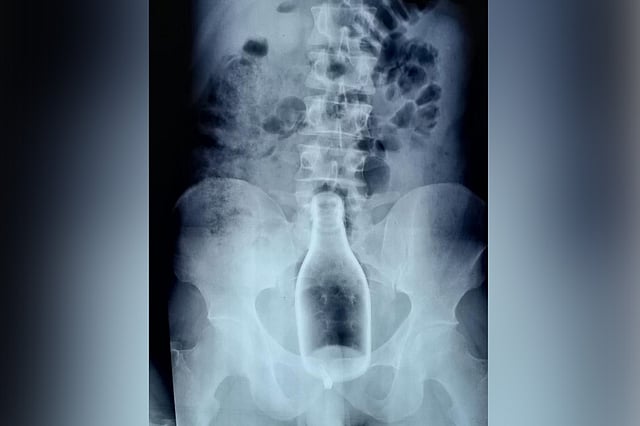

Doctors at the Nagapattinam Government hospital were in for a shock on May 27, moments after they received the X-ray of a 29-year-old patient. The resident from Nagore had arrived with complaints of pain in his rectum and uneasiness. The source of his discomfort soon became clear — a 250 ml glass bottle lodged in patient's the sigmoid colon.

"We were definitely shocked by what we were seeing," says Dr S Pandiyaraj, the General Surgeon at the hospital. "I had never seen something like this in my entire career so far," he adds.

"Ideally we wouldn't want to do the surgery without conducting a test for coronavirus. But this was a glass bottle and if it broke it could have caused severe internal damage," the surgeon says. "So we took the risk and immediately conducted the surgery. We gave the patient spinal anaesthesia to make him unconscious and managed to remove the bottle in a two-hour surgery," he adds.